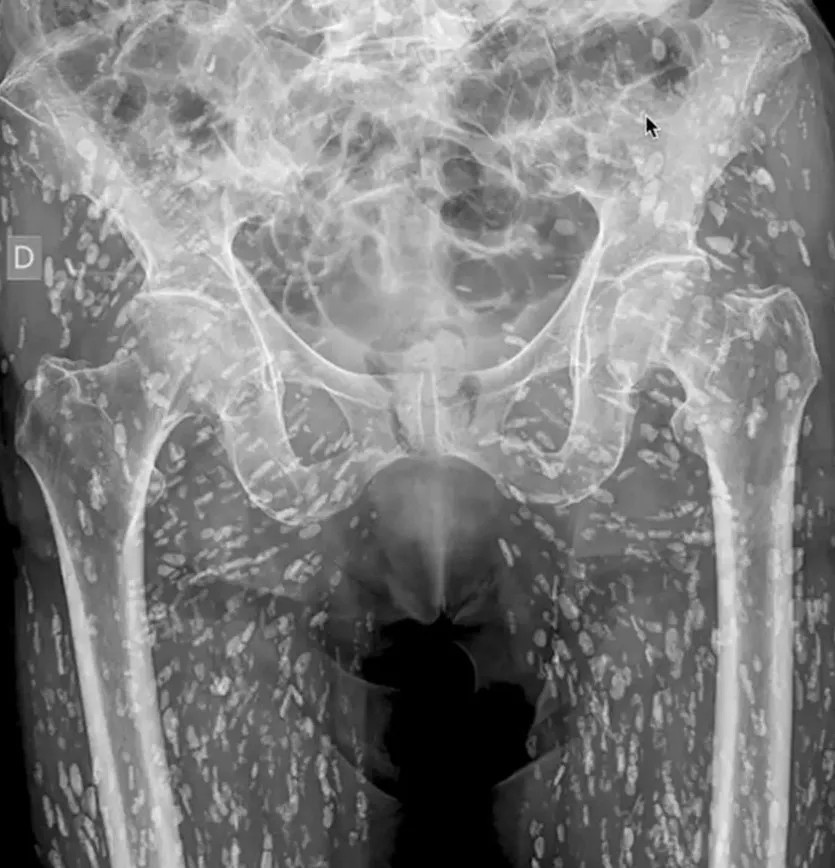

Phim chụp X-quang cho thấy một người đàn ông nhiễm hàng trăm trứng sán dây do thói quen ăn thịt lợn chưa chín kỹ.

Bác sĩ người Mỹ Sam Ghali đã chia sẻ thông tin sức khỏe của người đàn ông giấu tên và nói rằng đó là "một trong những phim chụp X-quang đáng sợ nhất mà tôi từng thấy". Vị bác sĩ nói thêm: "Đây là các nang ấu trùng của sán dây taenia solium còn được gọi là sán dây lợn".

Tình trạng đó xảy ra khi một người ăn thịt lợn sống hoặc chưa nấu chín dẫn tới nhiễm sán trong đường tiêu hóa. Những nang này có thể di chuyển khắp cơ thể con người. Ở bệnh nhân trên, các nang ấu trùng đã di chuyển rất nhiều đến các mô cơ và mô mềm ở hông và chân.

Người đàn ông tình cờ phát hiện ra bệnh khi đi chụp X-quang do bị ngã và đau hông. Trong trường hợp này, các nang không gây ra vấn đề đe dọa tính mạng. Nhưng trong một số ca, nang ấu trùng có thể gây ra bất ổn nghiêm trọng, đặc biệt khi di chuyển tới não. Bệnh ấu trùng sán dây thần kinh có nguy cơ dẫn đến các triệu chứng như đau đầu, lú lẫn, co giật, thậm chí tử vong.

Phim chụp X-quang của người đàn ông nhiễm sán dây lợn. Ảnh: X